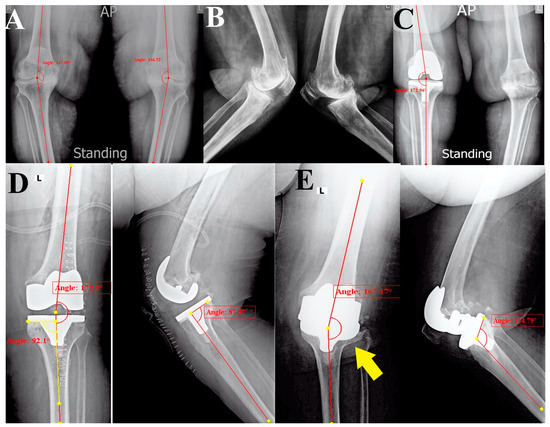

She had had her right side replaced using a posterior stabilized (PS) TKA implant without a stem four years ago, and the follow-up of her right TKA was uneventful, but she still complained of left knee pain. In September 2023, she presented for left-side TKA. Her preoperative radiographic evaluation showed well-positioned right TKA and left knee advanced OA with varus deformity (anatomical femorotibial angle (aFTA) of the varus was 21°) (Figure 1A–C).

The surgery was performed using a medial parapatellar approach under spinal anesthesia and tourniquet control. We used a cemented PS TKA implant without stems; the intraoperative course and the early postoperative period were uneventful. Immediate postoperative radiographs showed aFTA of valgus 7°, posterior tibial slope (TS) of 2°, and medial proximal tibial angle (MPTA) of 92°, indicating proper limb alignment and implant positioning (Figure 1D) [16].

Radiological: Plain radiographs (anteroposterior (AP) and lateral views) showed a valgus knee deformity (aFTA of valgus 13°) and PPF of the lateral tibial plateau with a loose tibial implant (classified as type ⅠB, according to Mayo Classification System [15]), as well as reversed TS of 25° (Figure 1E).

Figure 1. A series of initial radiographic evaluations (anteroposterior (AP) and lateral views); (A,B) the initial presentation had been more than four years ago with bilateral tricompartmental knee advanced osteoarthritis associated with varus deformity. (C) After having right knee TKA using a posterior stabilized prosthesis (four years ago). (D) Immediate postoperative radiographs after left TKA showed acceptable limb and individual implant alignment and positioning. (E) Three weeks postoperatively, catastrophic failure of the tibial component with lateral tibial plateau fracture (yellow arrow) and loosening of the tibial component.